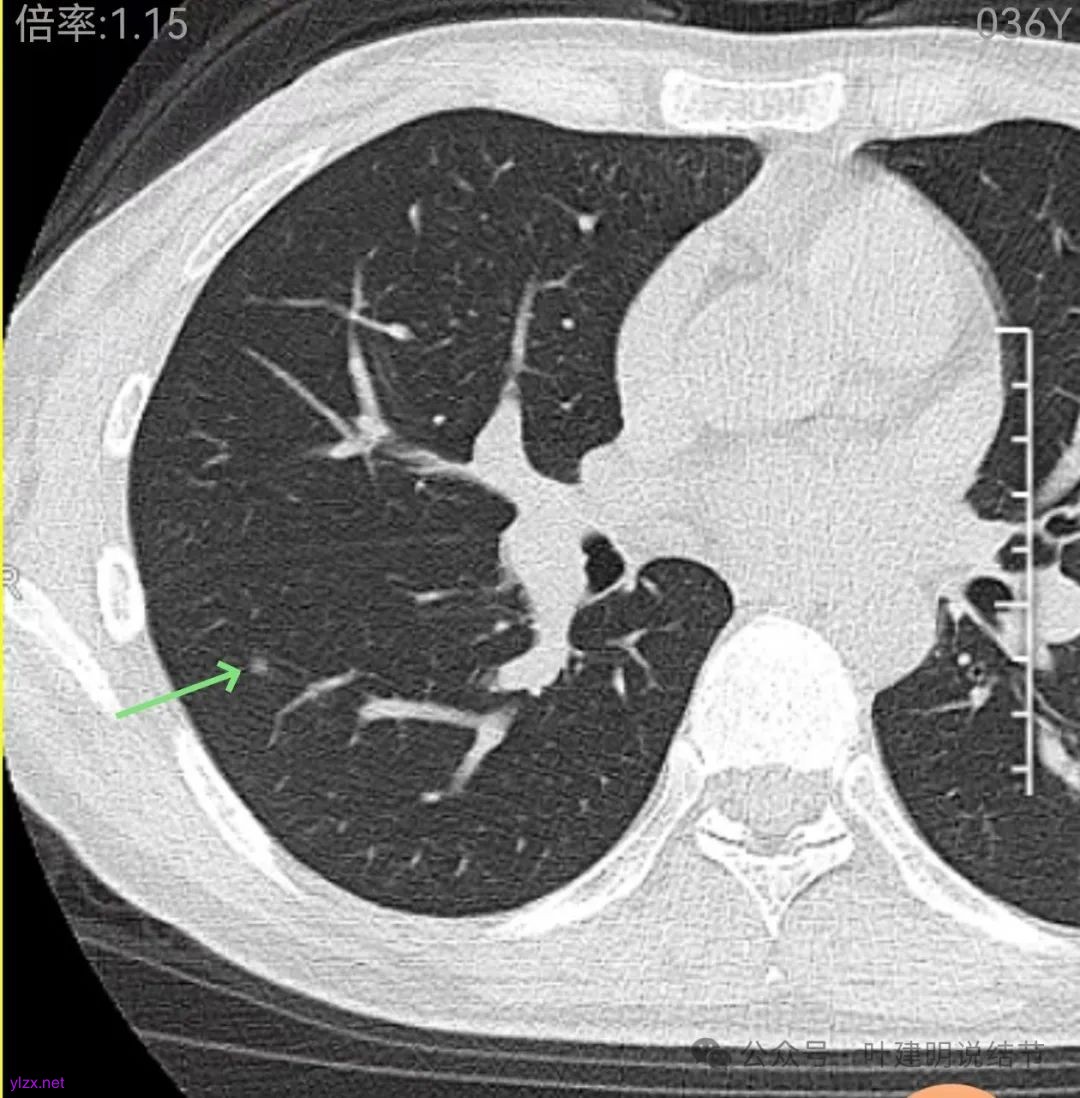

右下当时是很淡的,也显偏模糊的磨玻璃影。

右下此灶2023年时此层面淡而边显糊。

上图层面已经像混合密度了,表面毛糙不光滑,灶内密度不均,也有小空泡征的样子。

感觉这处(在上截图结节的下面点,邻近层面)不像前面病灶的延伸,否则这密度的变化有点突兀呀。